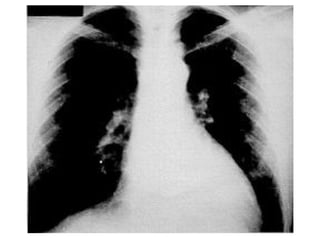

b.  Edema alveolar Cuando la  presión venosa  alcanza los  30 mm Hg  el líquido sobrepasa el espacio intersticial y escapa rellenando los alvéolos pulmonares, produciendo un patrón alveolar típico, con  lesiones condensantes ,  mal definidas , de  bordes imprecisos , que tienden a  coalescer  y que pueden aparecer  en cualquier área  de los pulmones.

Edema pulmonar. El edema del intersticio se traduce por borramiento de la trama vascular y presencia de líneas de Kerley. El edema alveolar da sombras de relleno que se disponen simétricamente alrededor de los hilios, produciendo una imagen en mariposa. El aumento de tamaño del corazón indica que en este caso el edema es cardiogénico.